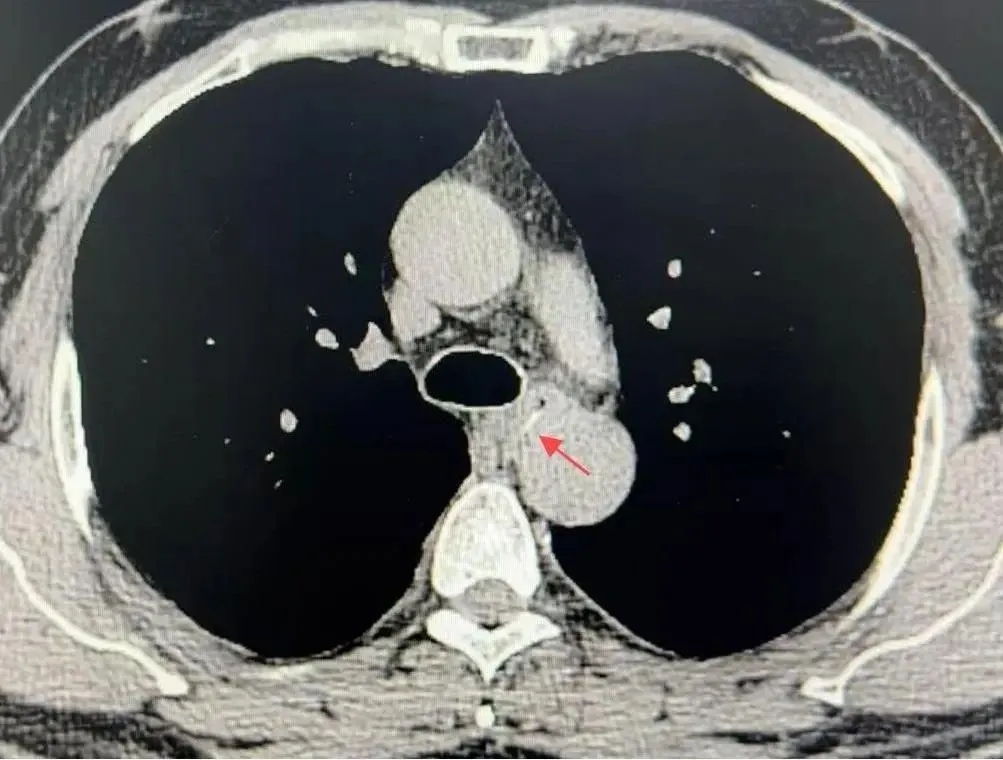

经过胸部CT检查,医生发现一根长约15毫米的鱼骨卡在了食管中段,而且鱼骨的尖端距离降段主动脉仅有4毫米,几乎就是一纸之隔(见图1)。

图1. CT显示鱼骨紧贴降主动脉

(红色箭头指示)

医生联系了影像科医生,通过CT三维重建技术明确了鱼骨与主动脉的解剖关系。结果显示,鱼骨尖端与主动脉切线平行,并未刺破主动脉,同时鱼骨也未刺破食管。